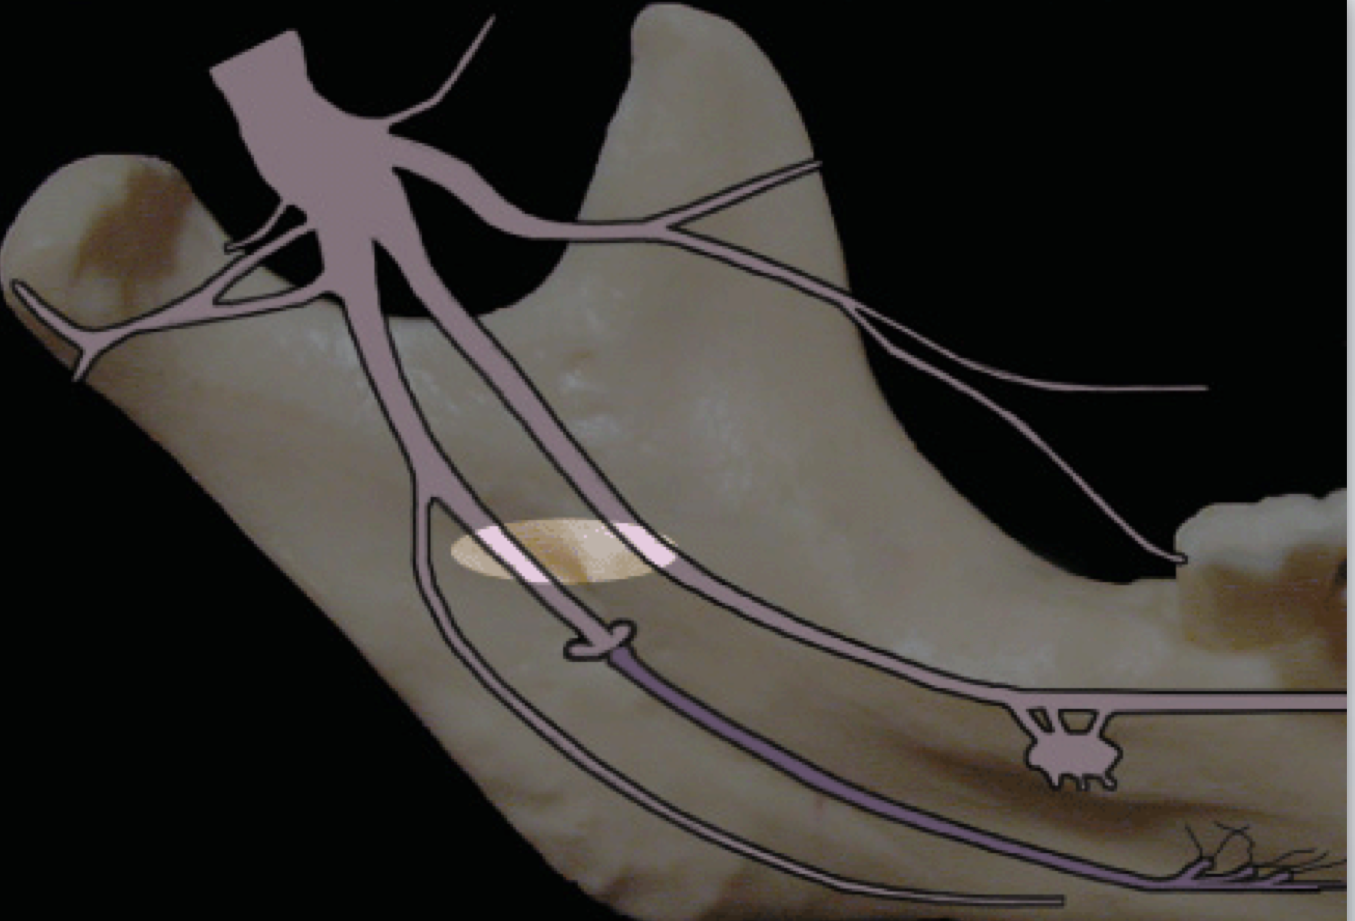

Accessory innervation (Mylohyoid nerve)

describe failure of IAN block and relationship to bifid inferior alveolar nerve/canal

A second mandibular foramen may exist

To correct: second injection inferior to the normal anatomical landmark

Accessory innervation

Can provide portion of pulpal innervation to mandibular teeth (most commonly in the mesial portion of the mandibular 1st molar or premolars)